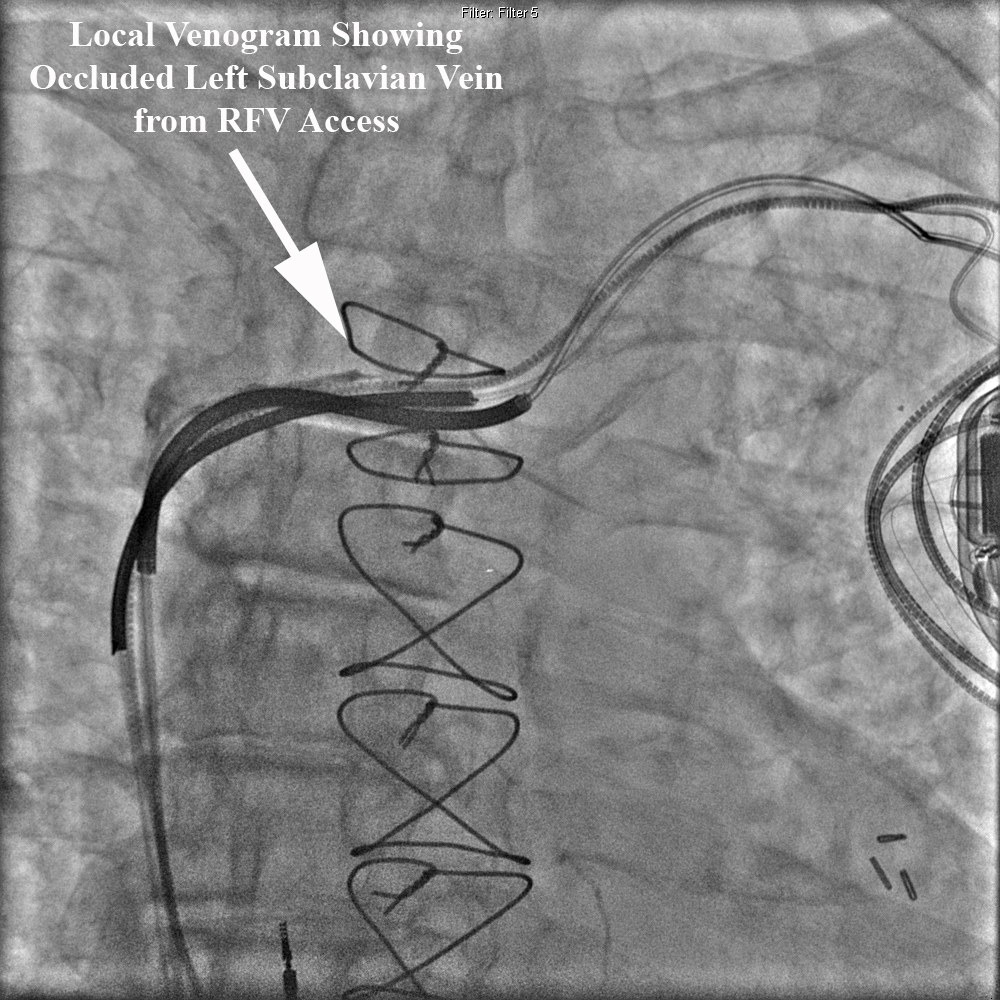

Right femoral venous access was obtained and a 5French deflectable octapolar EP catheter was used to document coronary sinus patency. At this point, access to the left subclavian vein was attempted with the EP catheter without success. A local venogram was then performed using a 5French multipurpose catheter and once again demonstrated an occluded left subclavian vein from the contralateral approach. See Figure below.